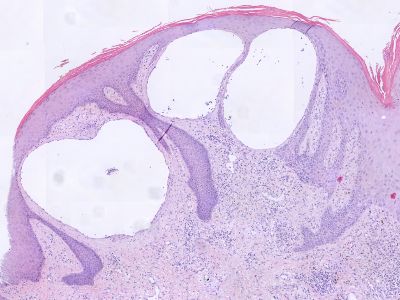

Histologie papillomatosis bij lymfoedeem

ingescande coupe (zoom)

Bron hoge resolutie PA-foto: Kevin Kwee en Afdeling Pathologie MUMC. Klik op de afbeelding om in te zoomen.